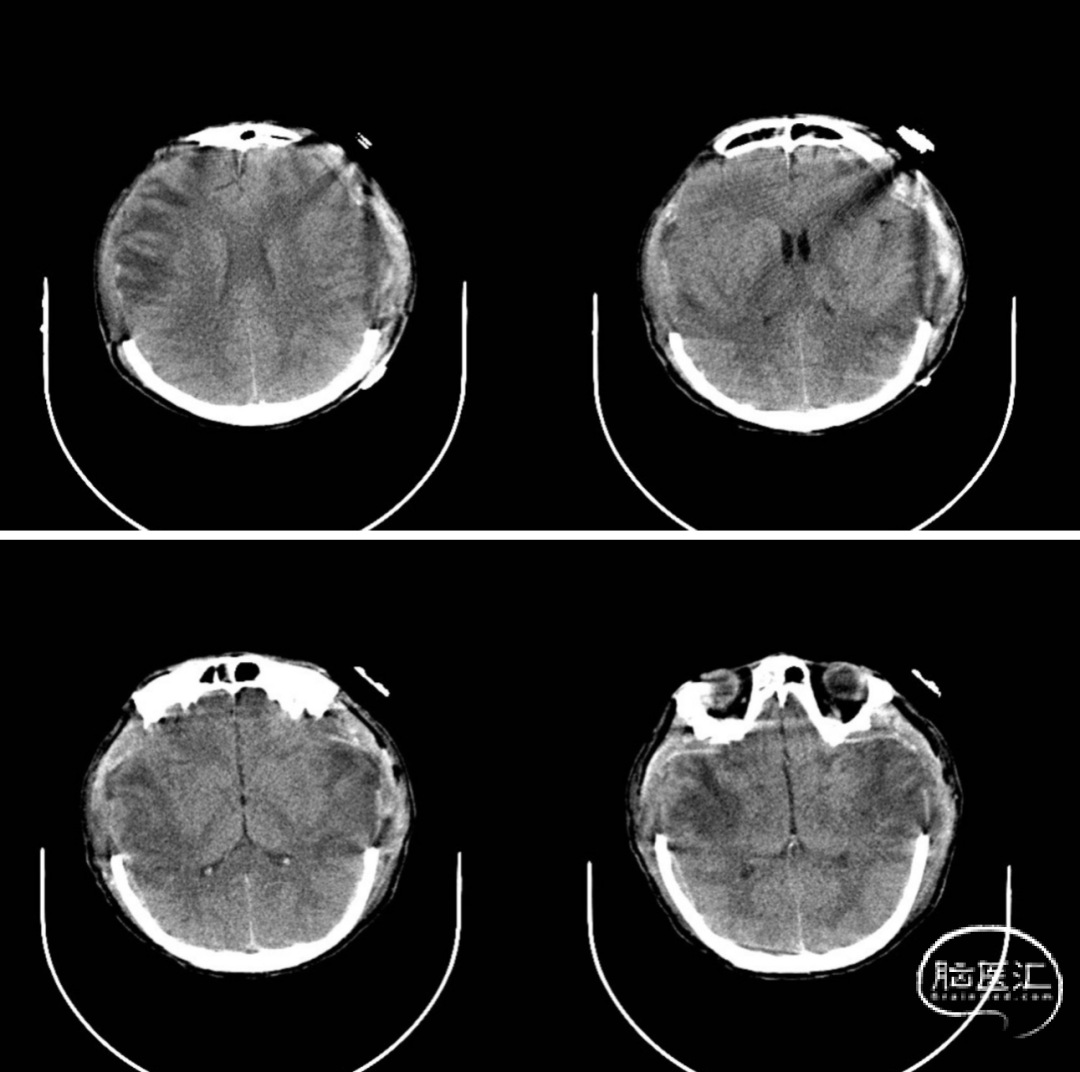

▲颅骨修补术前

▲颅骨修补术后